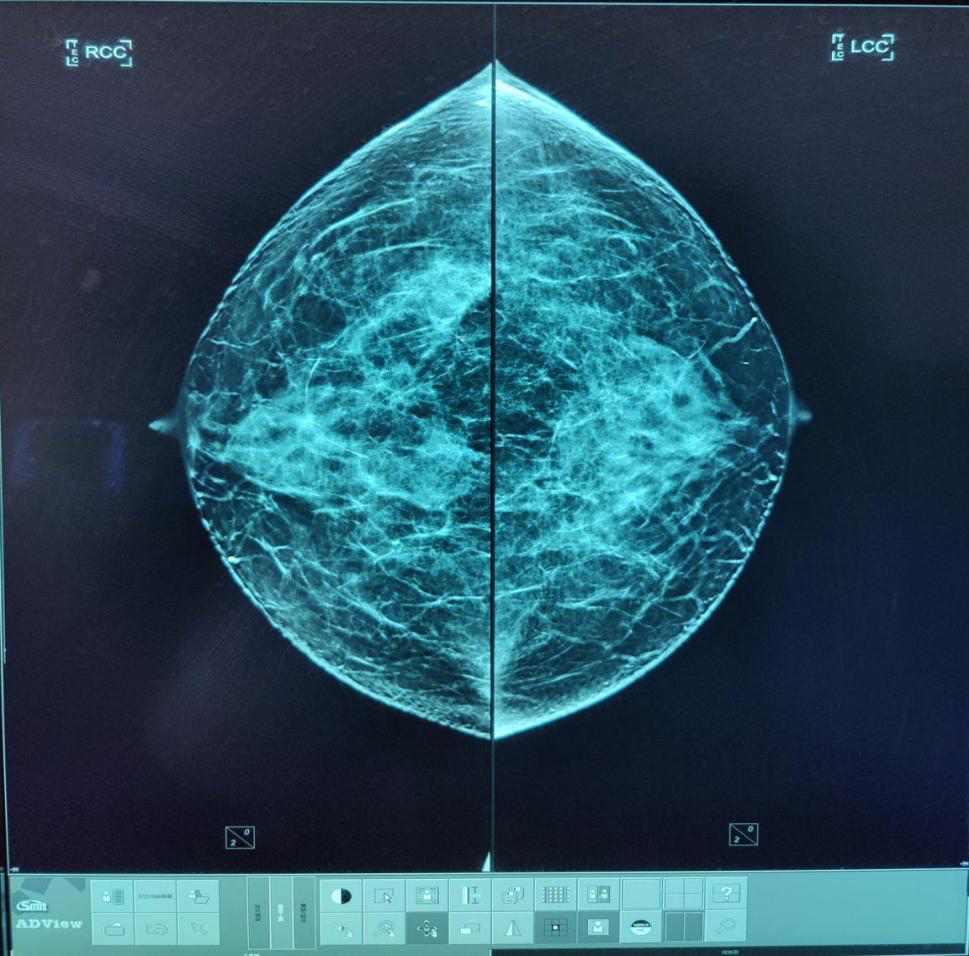

4月18日,集“筛查、诊断、3D定位活检穿刺”三个高端功能于一体的美国豪洛捷智能3D数字化乳腺X线摄影系统在玉溪市中医医院投入使用。

采用业内分辨率最高的非晶硒探测器,空间分辨率≥71p/mm,像素大小≤70um。

断层+传统2D乳腺摄影、断层+合成2D乳腺摄影、断层+传统2D+合成2D乳腺摄影三种成像模式,能够最大限度的显示乳腺细微结构及病变。

配备专业乳腺诊断工作站,工作站竖屏为分辨率达2KX2.5K的Barco医用专业灰阶竖屏屏,搭载豪洛捷数字化乳腺影像计算机辅助侦测系统(CAD),能很大程度避免乳腺钙化、肿块的漏诊。

美国FDA认定其为致密型乳腺的优选检查方法,其数字化乳腺断层摄影技术(digital breast tomosynthesis DBT)简称TOMO技术,是乳腺癌筛查首选的检查方法。

传统乳腺钼靶检查中,腺体组织会不同程度遮蔽病灶,而数字乳腺断层摄影可以通过对乳腺不同角度的多次摄影获取信息,有效区分正常腺体组织与病灶,更好发现一些隐匿的微小病变,并且对病变的边缘、边界显示清晰,可以提供更多的细节信息帮助对病变性质的判断。与此同时,TOMO技术并不增加射线剂量,患者可以放心接受这项检查。